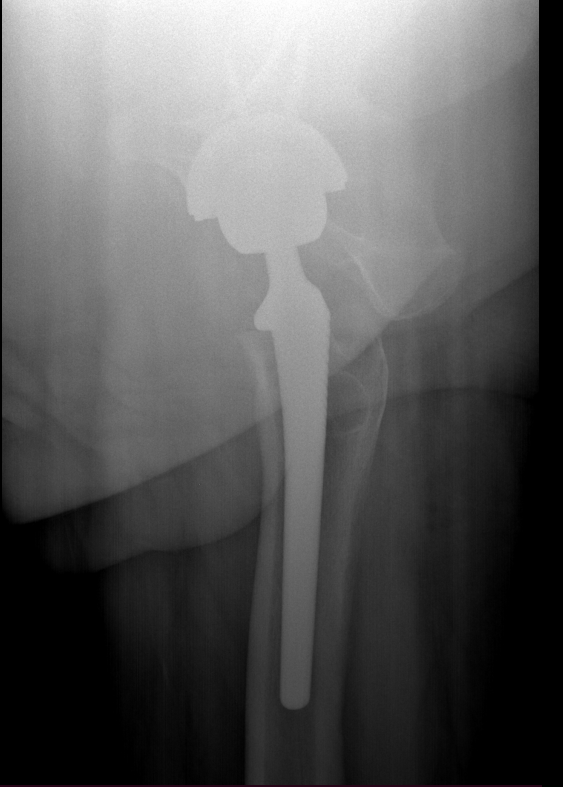

Diagnosis is made by evaluating medical history, physical examination and X-rays.

The surgery is performed under general anesthesia. During the procedure a surgical cut is made over the hip to expose the hip joint and the femur is dislocated from the acetabulum. The surface of the socket is cleaned and the damaged or arthritic bone is removed using a reamer. The acetabular component is inserted into the socket using screws or occasionally bone cement. A liner made of plastic, ceramic or metal is placed inside the acetabular component. The femur or thigh bone is then prepared by removing the arthritic bone using special instruments, to exactly fit the new metal femoral component. The femoral component is then inserted to the femur either by a press fit or using bone cement. Then the femoral head component made of metal or ceramic is placed on the femoral stem. All the new parts are secured in place using special cement. The muscles and tendons around the new joint are repaired and the incision is closed.